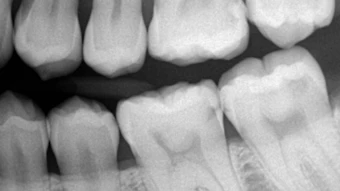

Goldberg: Unlike other caries detection systems, the Ortek ECD measures the conductivity of enamel. The ECD was specifically designed to help dental professionals diagnose and monitor early cavitated lesions in the pits and fissures located on the occlusal surfaces of posterior teeth. If the dentin-enamel junction is breached by demineralization, hydrostatic pressure that exists within dentinal tubules will allow minuscule amounts of conductive dentinal fluid to enter the breached enamel site, allowing the ECD to complete an electrical circuit.

Loss of mineral from enamel as a result of caries activity increases porous size and enamel porosity. As this demineralization increases, more dentinal fluid enters the breached site. The more fluid detected results in a higher current and an increasing digital caries score that is digitally displayed from 01–100. Intact tooth enamel is a good insulator and is electrically nonconductive. When the enamel at the bottom of a pit or fissure is intact, the circuit path is opened and no current can flow, indicating no cavitated lesion and a zero score.